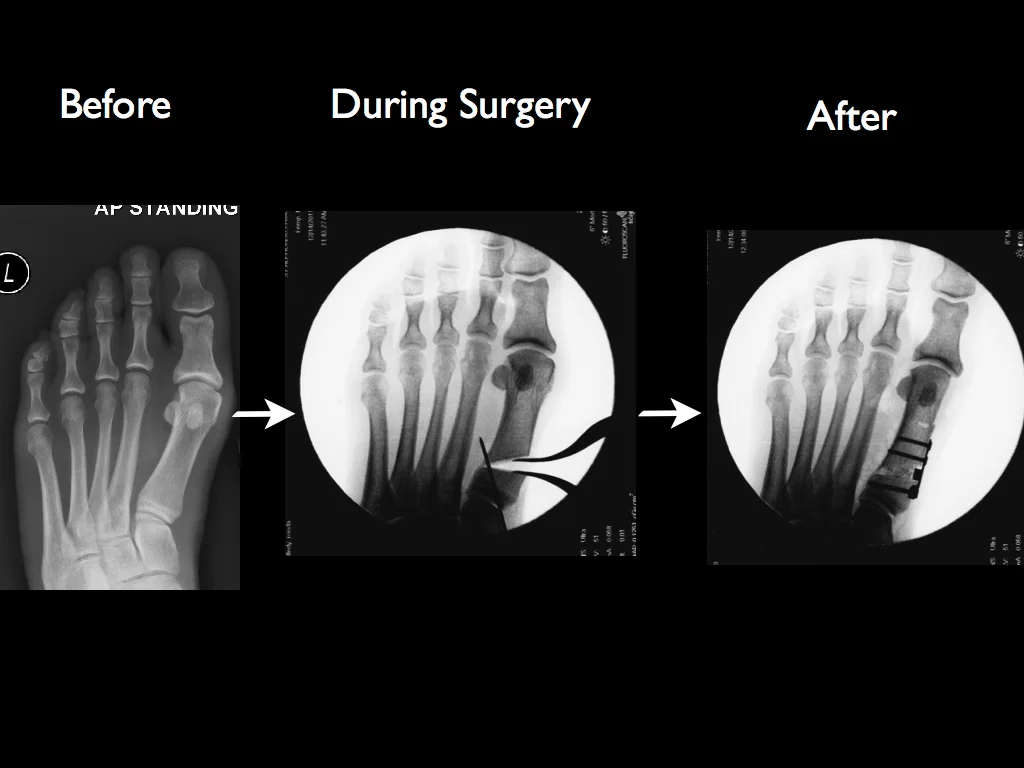

Hammer Toe Surgery Xray

Charcot Marie Causes Foot Deformities Such As Hammer Toes This Is An X Ray Of Someone Who Has Had Hammer Toe Su Hammer Toe Surgery Hammer Toe Foot Deformities